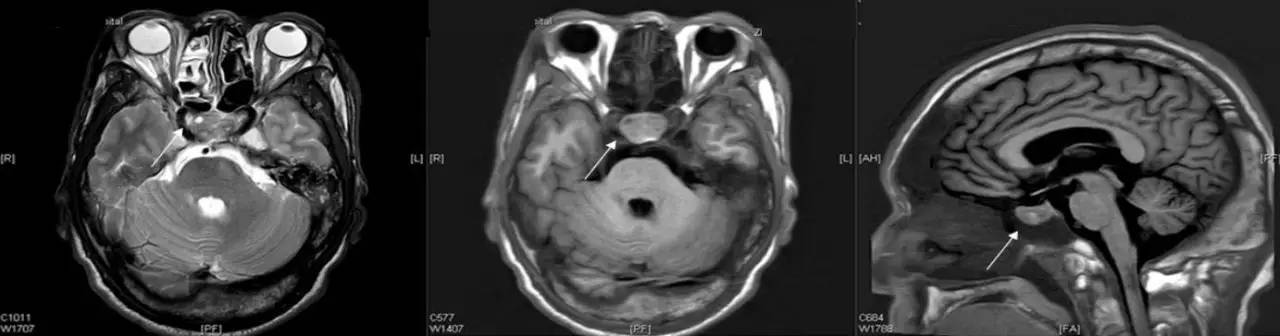

头颅MR

垂体增大,其内信号不均,可见斑片状长T1长T2信号影,边界清楚(图3)。

图3